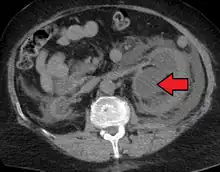

Massive hydronephrosis as marked by the arrow- Renal ultrasonography of hydronephrosis[16]